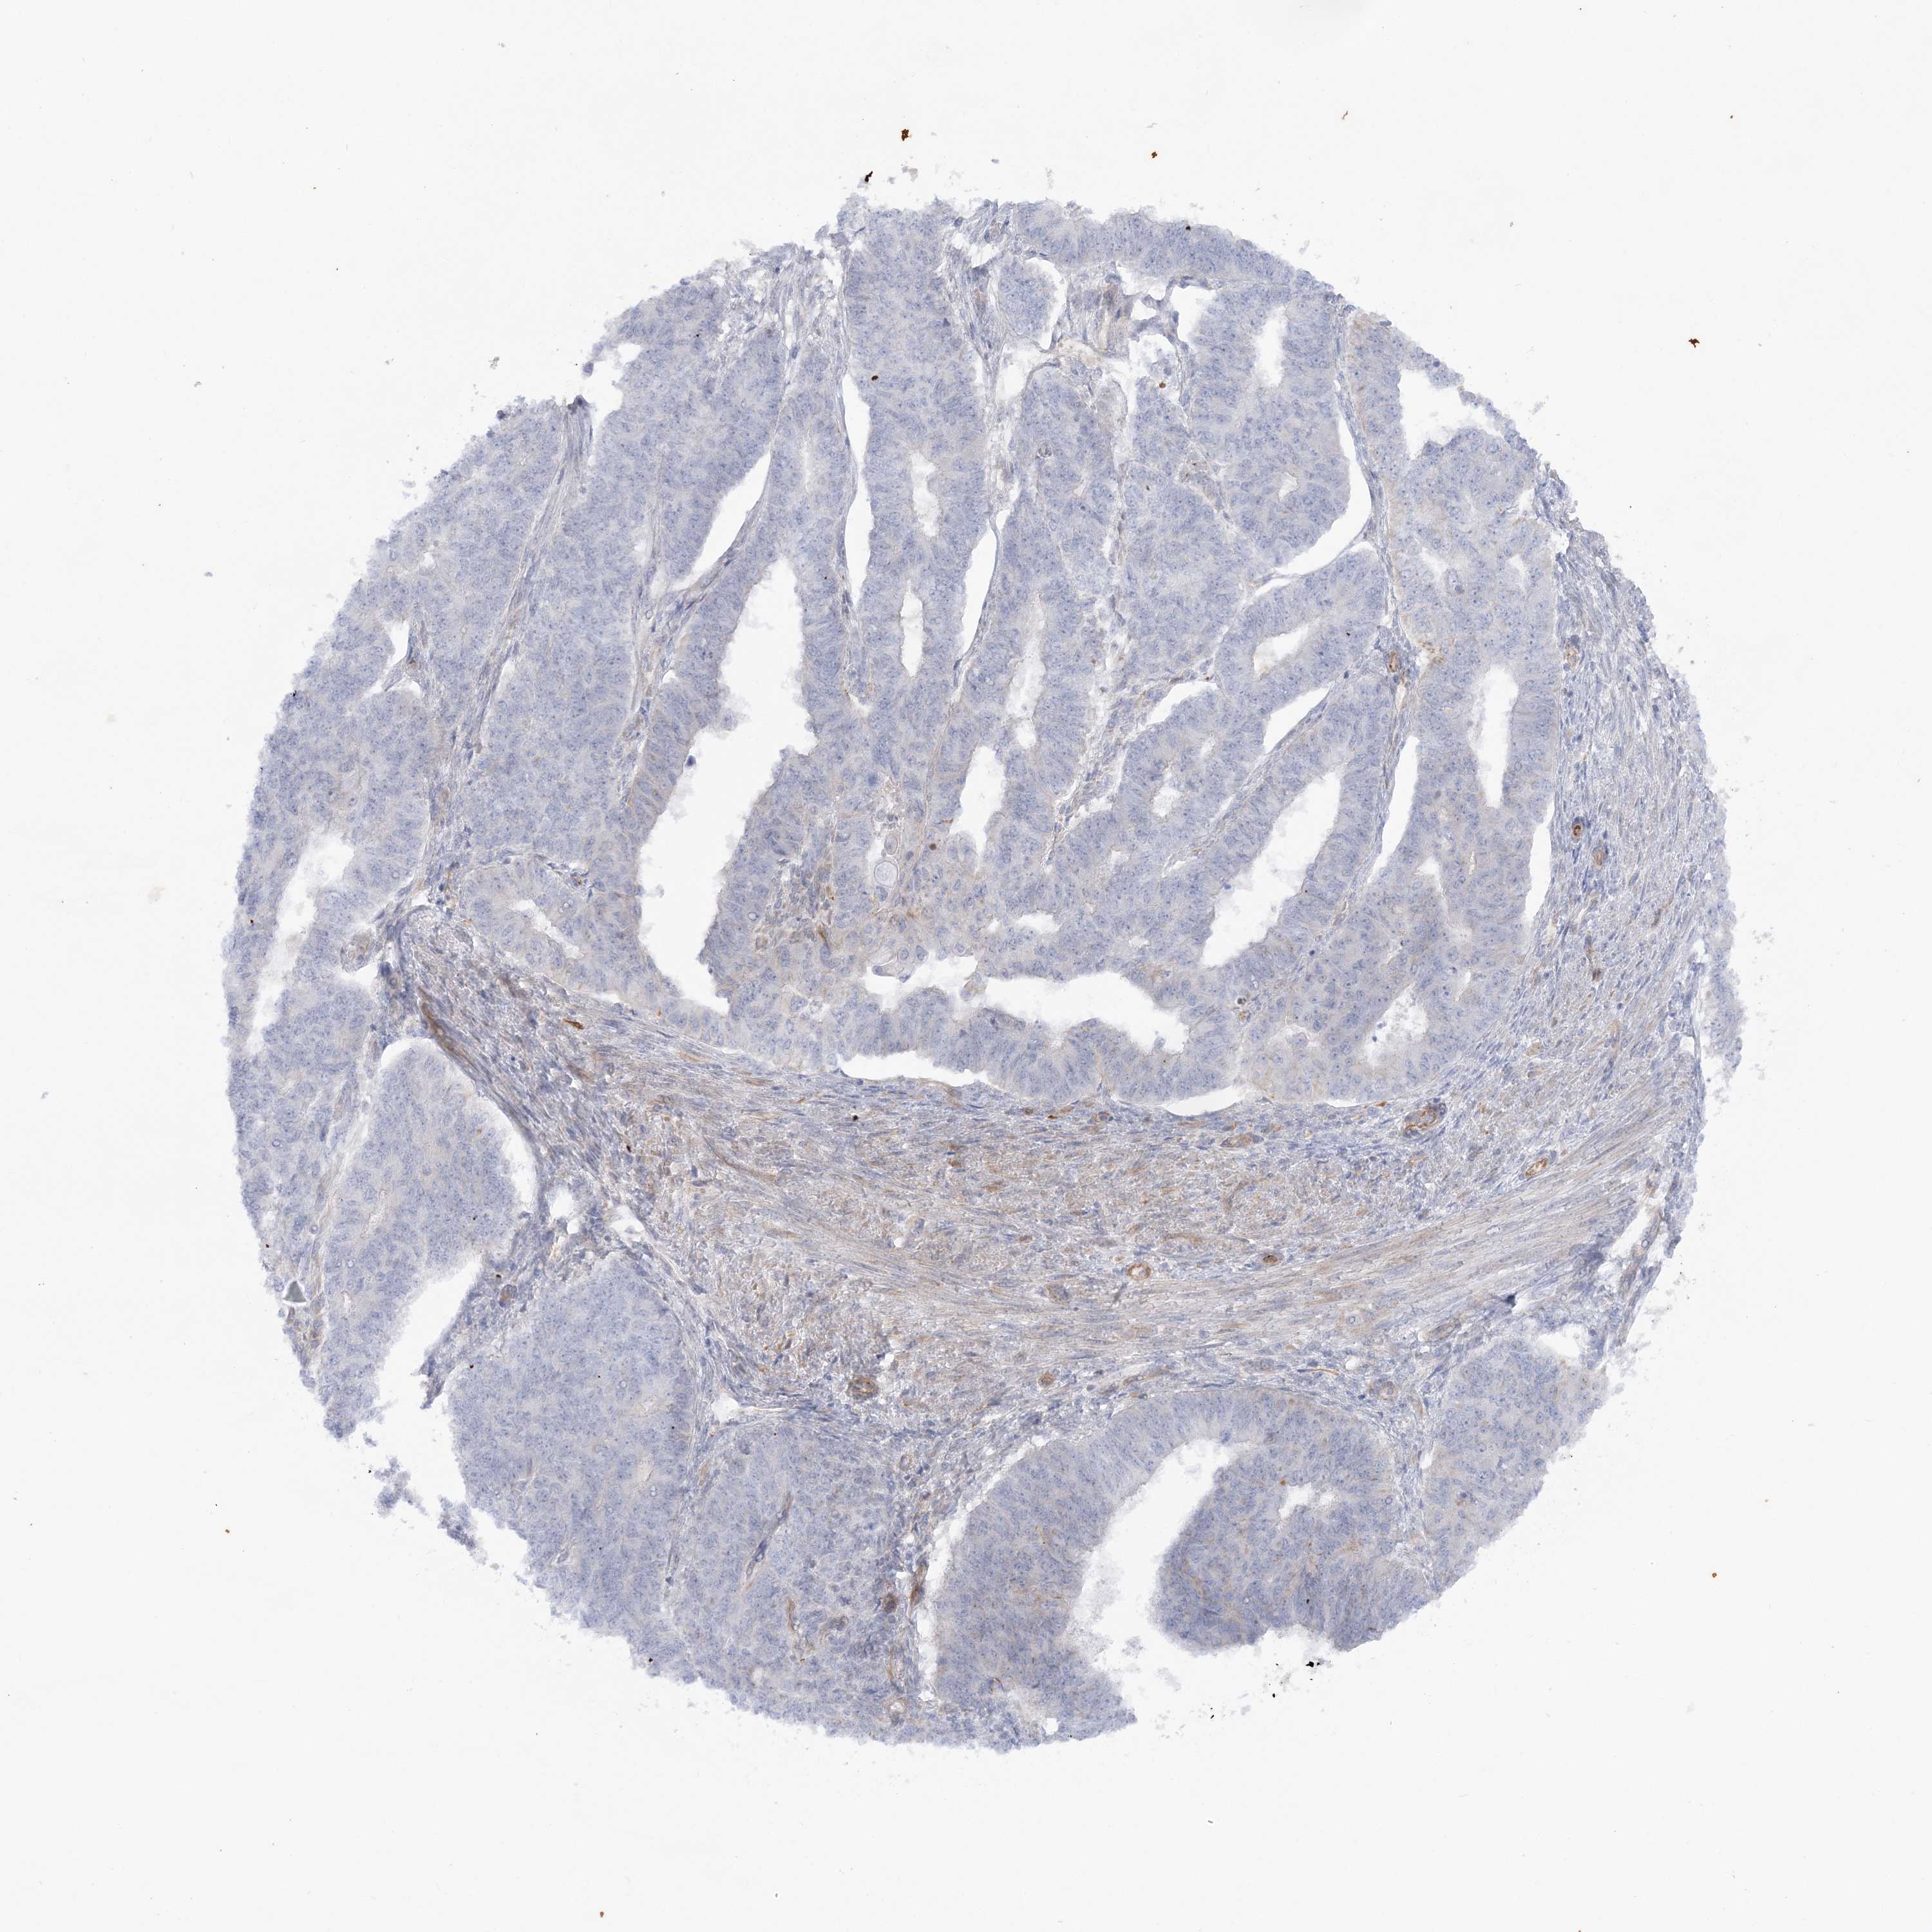

ENDOMETRIAL CANCER - Protein expressioni

A mouse-over function shows sample information and annotation data. Click on an image to view it in a full screen mode. Samples can be filtered based on level of antibody staining by selecting one or several of the following categories: high, medium, low and not detected. The assay and annotation is described here.

Note that samples used for immunohistochemistry by the Human Protein Atlas do not correspond to samples in the TCGA dataset.

Antibody stainingi

Antibody staining in the annotated cell types in the current human tissue is reported as not detected, low, medium, or high, based on conventional immunohistochemistry profiling in selected tissues. This score is based on the combination of the staining intensity and fraction of stained cells.

Each image is clickable and will lead to virtual microscopy that enables deeper exploration of all samples and also displays staining intensity scores, fraction scores and subcellular localization as well as patient and tissue information for each sample.

Antibody HPA036560

Antibody HPA036561

Staining

High

Medium

Low

Not detected

Intensity

Strong

Moderate

Weak

Negative

Quantity

>75%

75%-25%

<25%

None

Location

Nuclear

Cytoplasmic/membranous

Cytoplasmic/membranous,nuclear

Adenocarcinoma, NOS